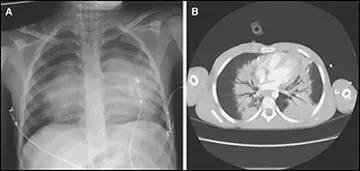

طب داخلی - صفحه 20